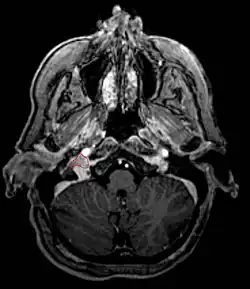

Przyzwojak (inaczej nerwiak przyzwojowy, łac. paraganglioma; często potocznie błędnie nazywany kłębczakiem[1]) – rzadko występujący, najczęściej niezłośliwy guz neuroendokrynny wywodzący się z ciałek przyzwojowych układu przywspółczulnego i układu współczulnego. Objawy i budowa histologiczna guzów przypomina guz chromochłonny nadnerczy; jeśli rdzeń nadnercza uznać za ciało przyzwojowe układu współczulnego, pheochromocytoma jest w istocie szczególnym typem przyzwojaka. Najczęstszą lokalizacją guza jest rozwidlenie tętnicy szyjnej wspólnej. Znajduje się tam kłębek szyjny (glomus caroticum).

Zdiagnozowanie przyzwojaka wymaga badania USG lub tomografii. Biopsja nie powinna być wykonywana ze względu na duże ukrwienie guza. Nie zawsze diagnostyka jest prosta, gdyż jak wspomniano na początku guzy te występują bardzo rzadko. Leczenie polega na operacyjnym usunięciu guza, co jeszcze niedawno wiązało się z dużym ryzykiem zgonu czy też powikłań pooperacyjnych. Postęp technik operacyjnych, w szczególności chirurgii naczyniowej, spowodował, że rokowanie jest stosunkowo dobre. W wypadku całkowitego usunięcia guza, następuje kompletne wyleczenie. Jeżeli guz usytuowany jest tak, że operacja jest niemożliwa, stosuje się radioterapię.